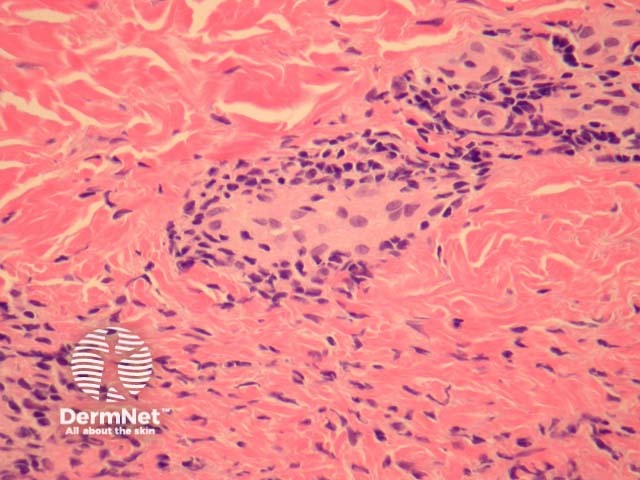

In perniosis, sections show acral skin with a dense superficial and deep lymphocytic infiltrate (figure 1). Subepidermal oedema may be marked. The characteristic feature is lymphocytic perivascular infiltrate within the dermis and sometimes extending to the subcutis (figures 2, 3). This is thought by some authors to represent the one true “lymphocytic vasculitis”, as there may be well established fibrinoid change and thrombosis can occur. There may be numerous eosinophils in early lesions (figure 4).

Figure 3

Chilblain lupus erythematosus: Frank lymphocytic vasculitis and interface changes are more common in chilblain lupus than in idiopathic chilblains (figure 5). A positive antinuclear antibody test favours chilblain lupus erythematosus.